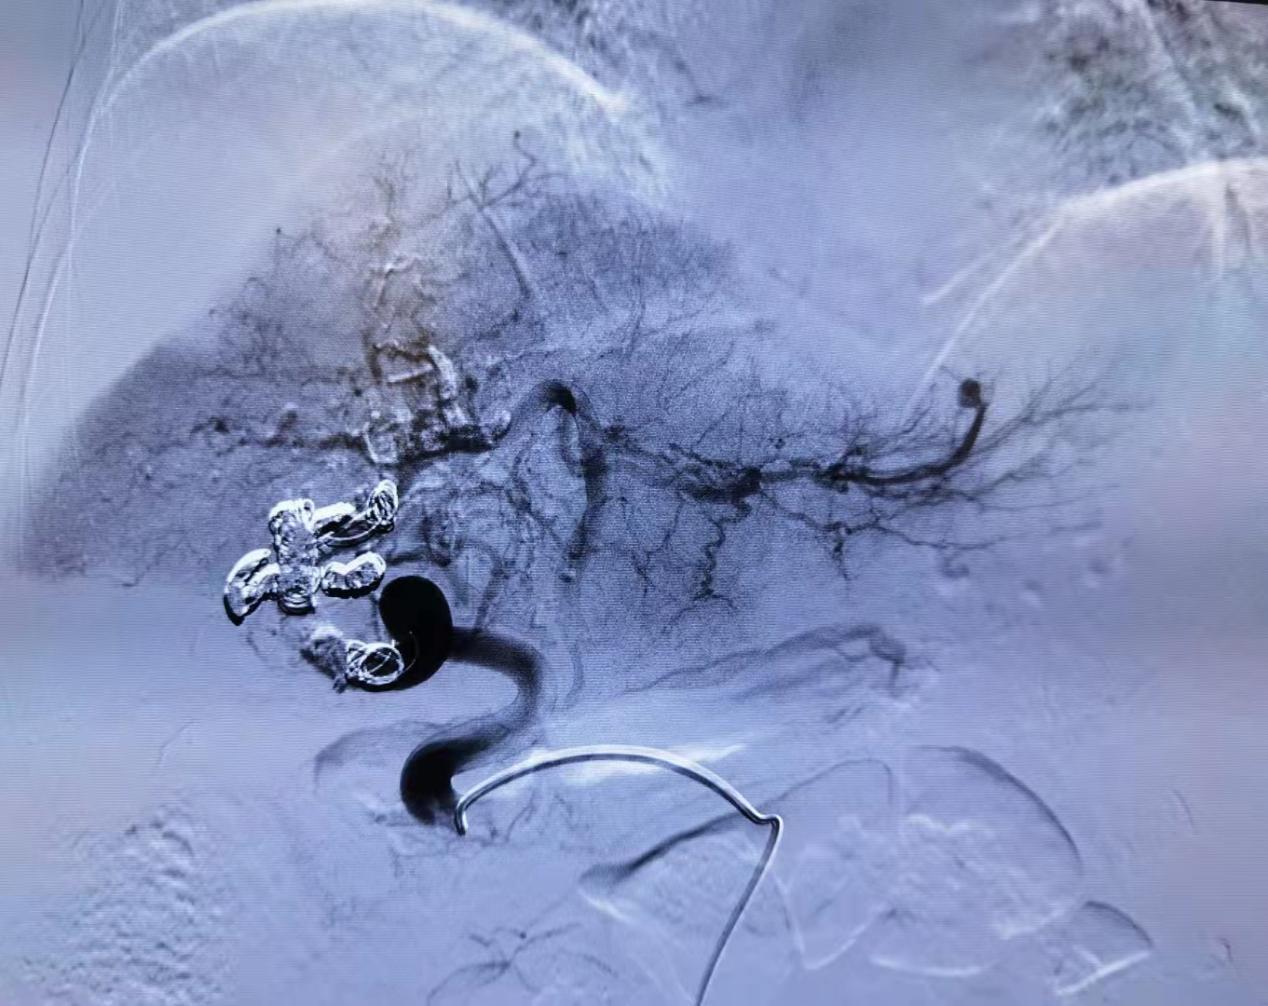

图五:栓塞瘘口后造影,门静脉不显影,肝动脉血供改善

肝动脉-门静脉瘘是肝动脉直接与门静脉沟通,高压的动脉血流直接流向门静脉,导致门静脉高压。此疾病如果未得到良好治疗,门脉高压持续进展,将导致大量腹水、下肢水肿、严重者出现食管胃底静脉曲张破裂出血,往往发病凶险、死亡率高。目前最为有效的治疗方法为介入治疗,栓塞靶血管,阻断肝动脉至门静脉血流,降低门脉压力。由于栓塞材料的不同,栓塞效果差异较大,其中弹簧圈联合组织胶技术的运用,类似“钢筋混凝土”的组合,效果最佳。但由于组织胶本身的特性,注射过快容易导致异位栓塞,注射过慢容易导致堵塞导管,手术难度大,成功率低,技术要求高。

此例手术难度极高,该患者存在瘘口巨大、多个瘘口等问题,没有处理好,可能导致肝动脉,甚至门静脉系统的异位栓塞等严重并发症。熊恺教授带领介入团队圆满完成手术,术后患者恢复良好。